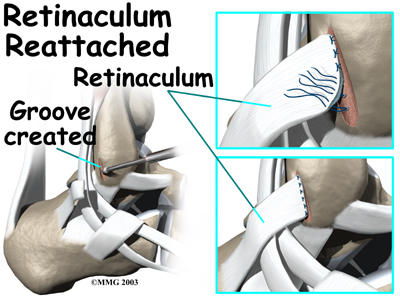

Retinaculum Repair

Retinaculum repair is gaining popularity. This procedure restores the normal anatomy of the retinaculum that covers and reinforces the tendon sheath around the peroneal tendons.

In surgery to repair the retinaculum, the surgeon first makes an along the back and lower edge of the fibula bone. This lets the surgeon see the spot where the retinaculum is torn.

The surgeon uses a burr to create a trough along the fibula bone next to the original attachment of the retinaculum. The torn edge of the retinaculum is then pulled into the trough and sutured in place. The skin is closed with stitches.